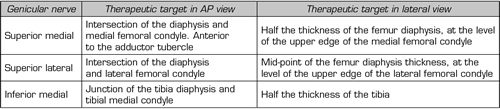

To perform a fluoroscopic-guided TRFGN, we need an anteroposterior (AP) and lateral view of the knee (Figure 2). First we place the patient in supine position with a pillow under the popliteal fossa (to make the patient more comfortable) (16). After performing asepsis and antisepsis of the knee, we proceed to locate the GN (Table II). SLGN is advancing the TFR needle toward the confluence of the lateral femoral diaphysis with the lateral femoral condyle in an AP view and at a mid-point of the femur in a lateral view. The SMGN is located by advancing the needle toward the confluence of the medial femoral diaphysis with the medial femoral condyle in an AP view and at a mid-point of the femur in a lateral view. Finally, the IMGN is located by advancing the needle toward the confluence of the medial tibial diaphysis with the tibial epicondyle in an AP view and at a midpoint of the tibia in a lateral view (16,17).

Table II. Location of genicular nerves guided by fluoroscopy

Good AP and lateral view is very important. In AP projection, the tibiofemoral joint should have a similar width on both sides of the knee with the interspace open (9). In lateral projection, there must be a correct overlap of both femoral condyles to perform a satisfactory blockage of the SMGN and SLGN (18).

Most authors take the references described above to locate these nerves by fluoroscopy, except Fonkoué et al. (18), who find that the therapeutic targets of SMGN and SLGN (in a lateral view) are at the junction of the upper edge of their respective femoral condyles with the posterior cortex of the femur diaphysis, and not in half the thickness of the femur, as described classically (9,10,13).

Because the success of the TRF of the genicular nerves depends on the correct location of the RF needle tip (as close as possible to the nerve), Know et al. (17) demonstrated with magnetic resonance imaging that the points used classically in fluoroscopy for ablation of the three genicular nerves (SMGN, SLGN and IMGN) are correct. They observed that GN passes through the intersection formed by the diaphyseal and metaphysis line of the distal femur or proximal tibia (SLGN 92 %, SMGN 88 % and IMGN 100 %).